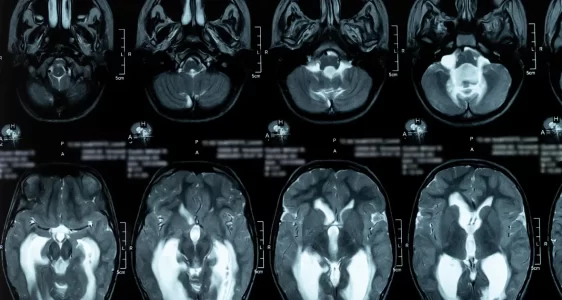

Hidrosefali, beyin omurilik sıvısının (BOS) normalden fazla üretilmesi veya akışının engellenmesi sonucu beyinde birikmesiyle ortaya çıkan ciddi bir rahatsızlıktır. Bu durum, kafa içi basıncın artmasına yol açarak baş ağrısı, bulantı, görme bozukluğu, yürüme güçlüğü, hafıza kaybı ve gelişim geriliği gibi belirtilerle kendini gösterebilir. Tedavi edilmediğinde kalıcı beyin hasarı ve yaşamı tehdit eden sonuçlar doğurabilir.